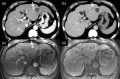

MRI is widely used in clinical practice for detecting liver diseases. Since the introduction of gadoxetic acid, MRI has become the most effective modality for the detection and characterization of focal liver lesions. According to previous meta-analyses, the area under the receiver operating characteristic curve (AUROC) was 0.97-0.99 for the diagnosis of small hepatocellular carcinoma (≥ 2 cm) by gadoxetic-acid-enhanced MRI. Moreover, the AUROC for the diagnosis of colorectal liver metastases was significantly high (0.98). Despite gadoxetic acid's drawbacks, its clinical utility outweighs them, making it the contrast agent of choice in routine liver MRIs. Moreover, clinically, liver MRI has become more prevalent for a quantitative assessment. Liver fibrosis can be evaluated using MR elastography; whereas, hepatic steatosis and iron overload can be evaluated using proton density fat fraction, with high accuracy and reproducibility. This article reviewed the usefulness of liver MRI, which can be a comprehensive imaging modality in clinical practice.